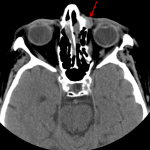

- Acute right Le Fort type I and II and left Le Fort type I, II, and III fractures with a nondisplaced left zygomatic arch fracture, fractures of the medial and inferior walls of the right orbit, fractures of all walls of the left orbit, fractures of all walls of both maxillary sinuses, fracture of the nasal septum, comminuted bilateral nasal arch fractures extending to the nasofrontal suture, and bilateral pterygoid plate fractures

- Bilateral nasoorbitoethmoid fractures with multiple bilateral ethmoid fractures in addition to the above discussed fractures

- Left greater than right retrobulbar hemorrhage with left proptosis

- Bilateral maxillary, ethmoid, and sphenoid hemosinus

- Extensive facial swelling/contusion and subcutaneous gas

- Heavy atherosclerotic calcification of the cavernous carotid arteries

Acute right Le Fort type I and II and left Le Fort type I, II, and III fractures including a nondisplaced left zygomatic arch fracture. Additionally there are bilateral nasoorbitoethmoid fractures. Fractures notably involve the bilateral infraorbital foramina and nasolacrimal canals.

Left greater than right retrobulbar hemorrhage with left proptosis.

Bilateral maxillary, ethmoid, and sphenoid hemosinus.